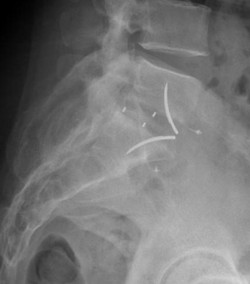

Cage vue de profil

La cage intervertébrale en place

Radiographie de profil

La perte sanguine durant l’intervention est variable en fonction du patient, de l’étendue de l’arthrodèse, de la durée d’intervention et des complications éventuelles. Elle peut être compensée par une autotransfusion (don de son propre sang avant l’intervention), une prise d’érythropoïétine (médicament qui stimule la fabrication des globules rouges) avant l’intervention. Une transfusion peut malgré tout être nécessaire, elle est plus rare aujourd’hui car on utilise pendant l’intervention un récupérateur de sang (autotransfusion).